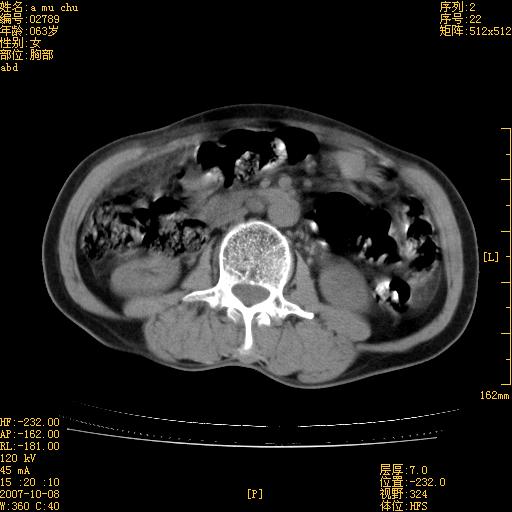

以下是引用王维浦在2007-10-17 21:02:00的发言:[br]胆囊增大,囊壁明显不规则增厚,邻近肝组织浸润,肝内外胆管无扩张。诊断:胆囊ca;[br]胰头软组织肿块影,考虑是由转移肿大的胰后淋巴结、没有肠道准备的十二指肠及胰头共同形成。[br]

以下是引用zhangzexing在2007-10-18 7:13:00的发言:[br]支持胰头占位,慢性胆囊炎. 2.肝左叶前外侧段占位,血管瘤?建议增强

以下是引用影像实习生在2007-10-17 19:49:00的发言:[br]支持胰头占位,慢性胆囊炎. 2.肝左叶前外侧段占位,血管瘤?建议增强.

以下是引用刘振江在2007-10-17 19:42:00的发言:[br]没有增强,胰头癌?胆囊及肝左叶占位?